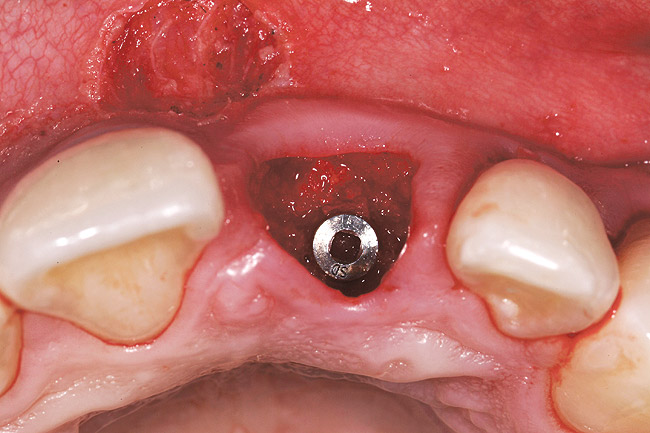

Figure 23  Case Three Atraumatic extraction, left central incisor.

Figure 23

A 24-year-old non-smoking man presented for treatment of a horizontally fractured left central incisor (Figure 21 and Figure 22). The patient requested to have an implant placed to replace the left central incisor as to not have any damage to the adjacent dentition.

Complicating the treatment site was the apically positioned facial height of contour at the left central incisor, and the adjacent left lateral incisor (Figure 21.) Additional sites of recession were present throughout the oral cavity and were to be addressed by the tunnel grafting procedure previously outlined.

The patient opted for the third option. After administration of an appropriate local anesthetic, a frenectomy was performed using a Nd:Yag laser. This would allow for the loosening of the facial tissues and the coronal repositioning of the pouch at the termination of the procedure. After the frenectomy, the left central incisor was removed by an atraumatic technique preserving the soft tissue emergence profile (Figure 23). Debridement of the extraction socket preceded atraumatic site preparation techniques. A 3.5-mm diameter by 13-mm tapered implant (Prima Connect, Keystone Dental, www.keystonedental.com) was placed to the appropriate depth measurements planned.38,39

Once the implant was seated, the cover screw was placed, and the facial defect at the buccal aspect of the implant was corrected using mineralized, large-particle cancellous chips (Lifenet, www.lifenet.org) and a solution of PRP, forming a graft/PRP gel complex. The graft complex was heavily condensed into the void present, to the level of the facial aspect of the polished collar on the implant (Figure 24).